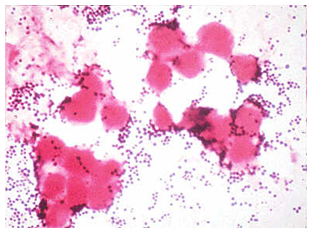

Staphylococci are facultative anaerobes that grow by anaerobic respiration or by fermentation that yields principally lactic acid. S. aureus can grow at a temperature range of 15oC-45oC and at NaCl concentration as high as 15%.1 Staphylococci are non-motile, non-spore forming and catalase positive. Their cell wall contains peptidoglycan and teichoic acid.4 Staphylococcus aureus often produce golden yellow colonies, often with hemolysis when grown on blood agar plates.5 More than 90% of S. aureus are resistant to the beta-lactamase- resistant penicillin such as methicillin, Nafcillin and Oxacillin, by virtue of changes in the penicillin-binding proteins in their cell membranes. These strains are commonly known as Methicillin resistant S. aureus (MRSA) (Figure 1).

Figure 1 Gram stain of Staphylococcus aureus in pustular exudates.

6